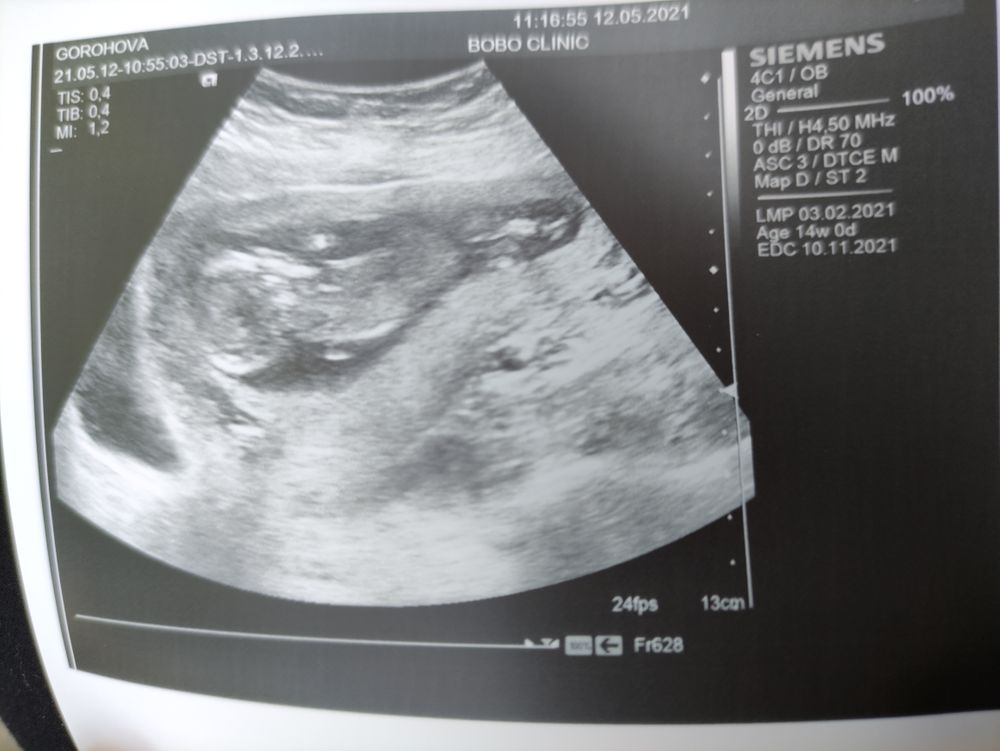

Оля Горохова, у меня первое фото практически такое же,не любят они ультразвук. Потом уже привык и позирует)